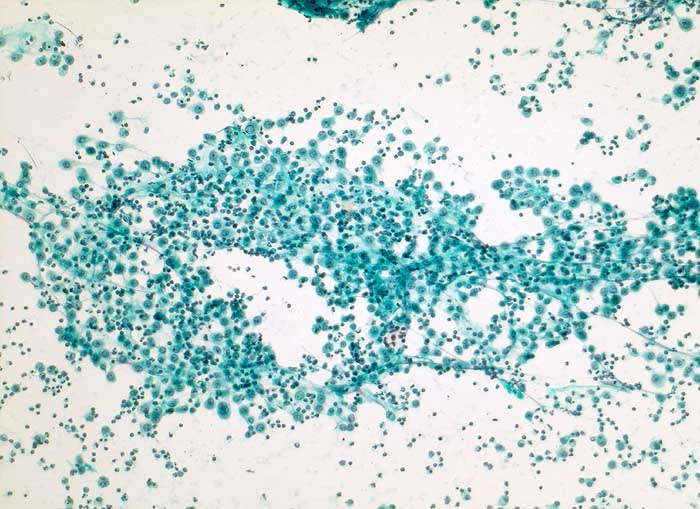

PathoPic – image database / PathoPic ID 5402 - reaktiv veränderte Mesothelien

reaktiv veränderte Mesothelien

Aszites

Körperhöhlen, Serosa

Aszites: Flächenhafte lockere Verbände grossleibiger aktivierter Mesothelzellen und zahlreiche Entzündungszellen.

Dieses immunhistochemische Markerprofil, insbesondere die deutliche Positivität für den Mesothel-Marker Calretinin und fehlende Expression des Epithelmarkers Ber-EP4, passen am ehesten zu Zellen mesothelialen Ursprungs. Auch Zytokeratin 7 wird in normalen Mesothelien typischerweise exprimiert. Insgesamt sprechen die Befunde für ausgeprägte reaktive Veränderungen und gegen ein Karzinom. Insbesondere bei Leberzirrhose werden gelegentlich schwere reaktive Mesothelveränderungen im Aszites beobachtet, die zytologisch ein Karzinom vortäuschen können.

Zytologie

100